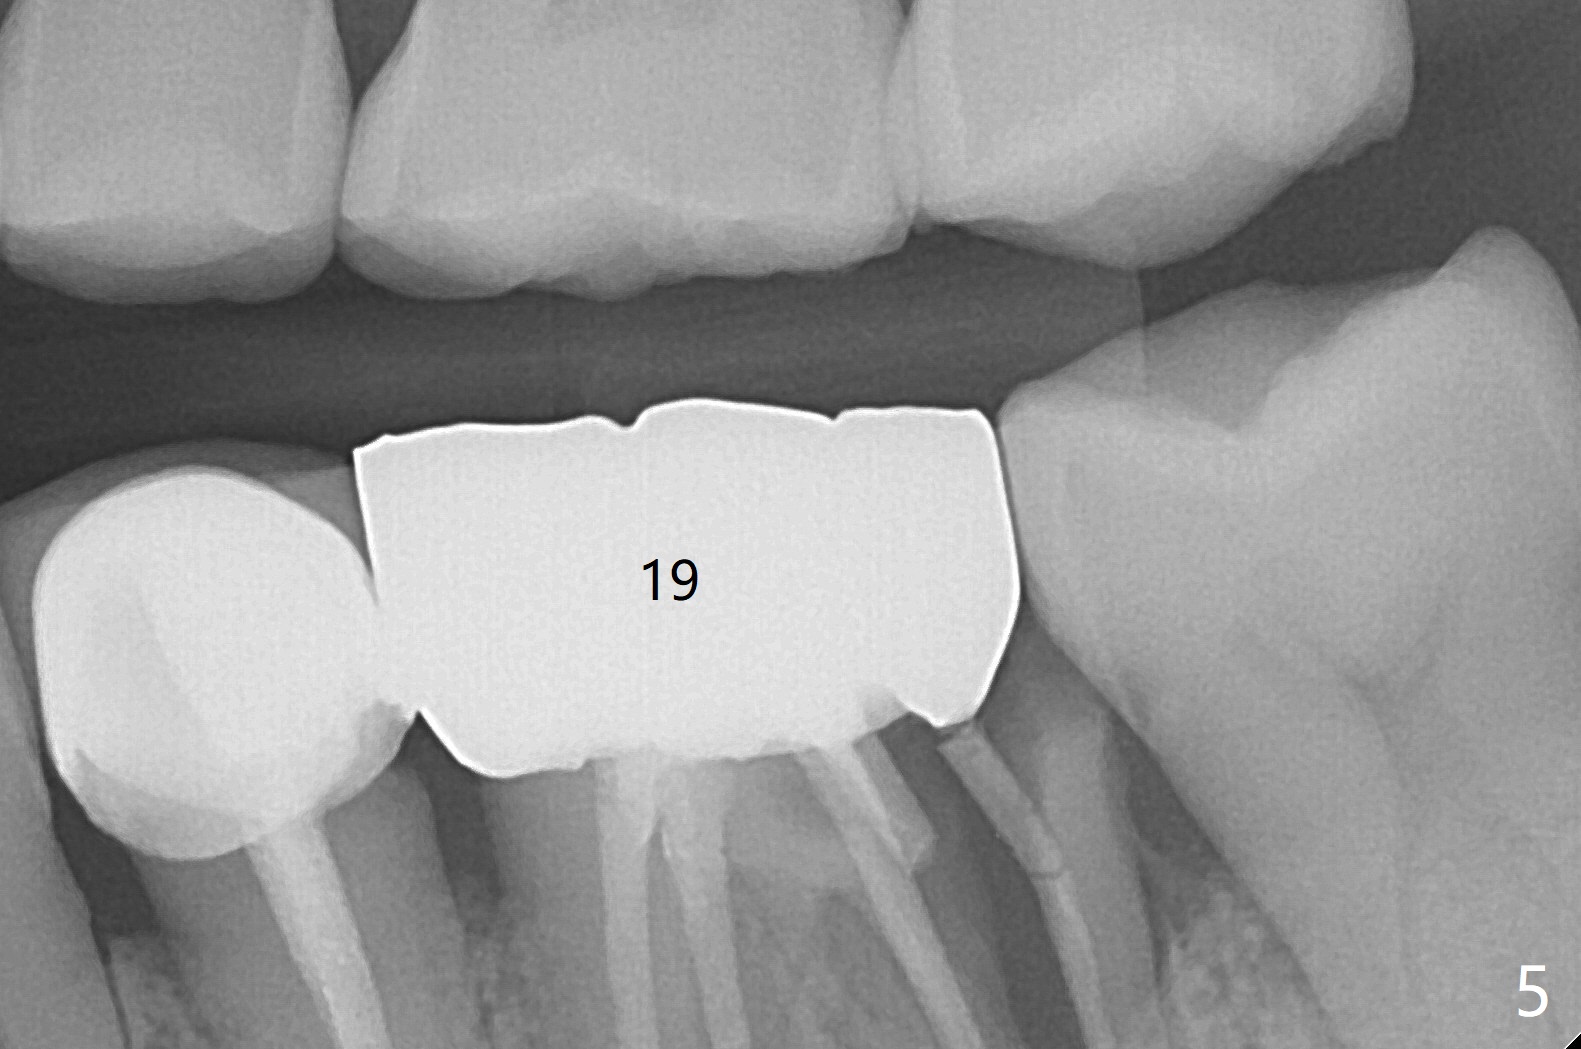

In spite of underprep (4.0x8.5 mm last drill), a 5x8.5 mm implant is placed at #2 with insertion torque ~ 15 Ncm (Fig.1). In addition to the large defect post implant removal with 4.5 month bone graft, he is a heavy gagger with limited mouth opening. Drill cylinders may not engage the metal sleeve precisely. A 5.5x4 mm healing abutment is placed with low emergency profile. The procedure, although difficult, finishes in a timely manner. Otherwise it would be a disaster for the patient and operator. PA taken 1 month postop shows slightly subcrestal placement (Fig.2). When a cemented abutment is placed 4 months postop, there is tenderness. In fact the implant is mobile. A 8x5 mm healing abutment is placed. Nine months postop, the implant remains slightly mobile (Fig.3); a healing screw is placed. The tooth #3 has sign and symptom of crack 13 months postop (Fig.4), related to root fracture of #19 (Fig.5, bruxism). In fact the tooth cracks nonsalvageable post RCT, 9 months post #2 healing screw, 21 months postop. Socket preservation will be carried out with sticky bone and PRF, while #2 implant will be uncovered, followed by placement of a short cemented abutment to hold periodontal dressing. Upper Molar Immediate Implant, Trajectory Xin Wei, DDS, PhD, MS 1st edition 11/27/2018, last revision 07/03/2021